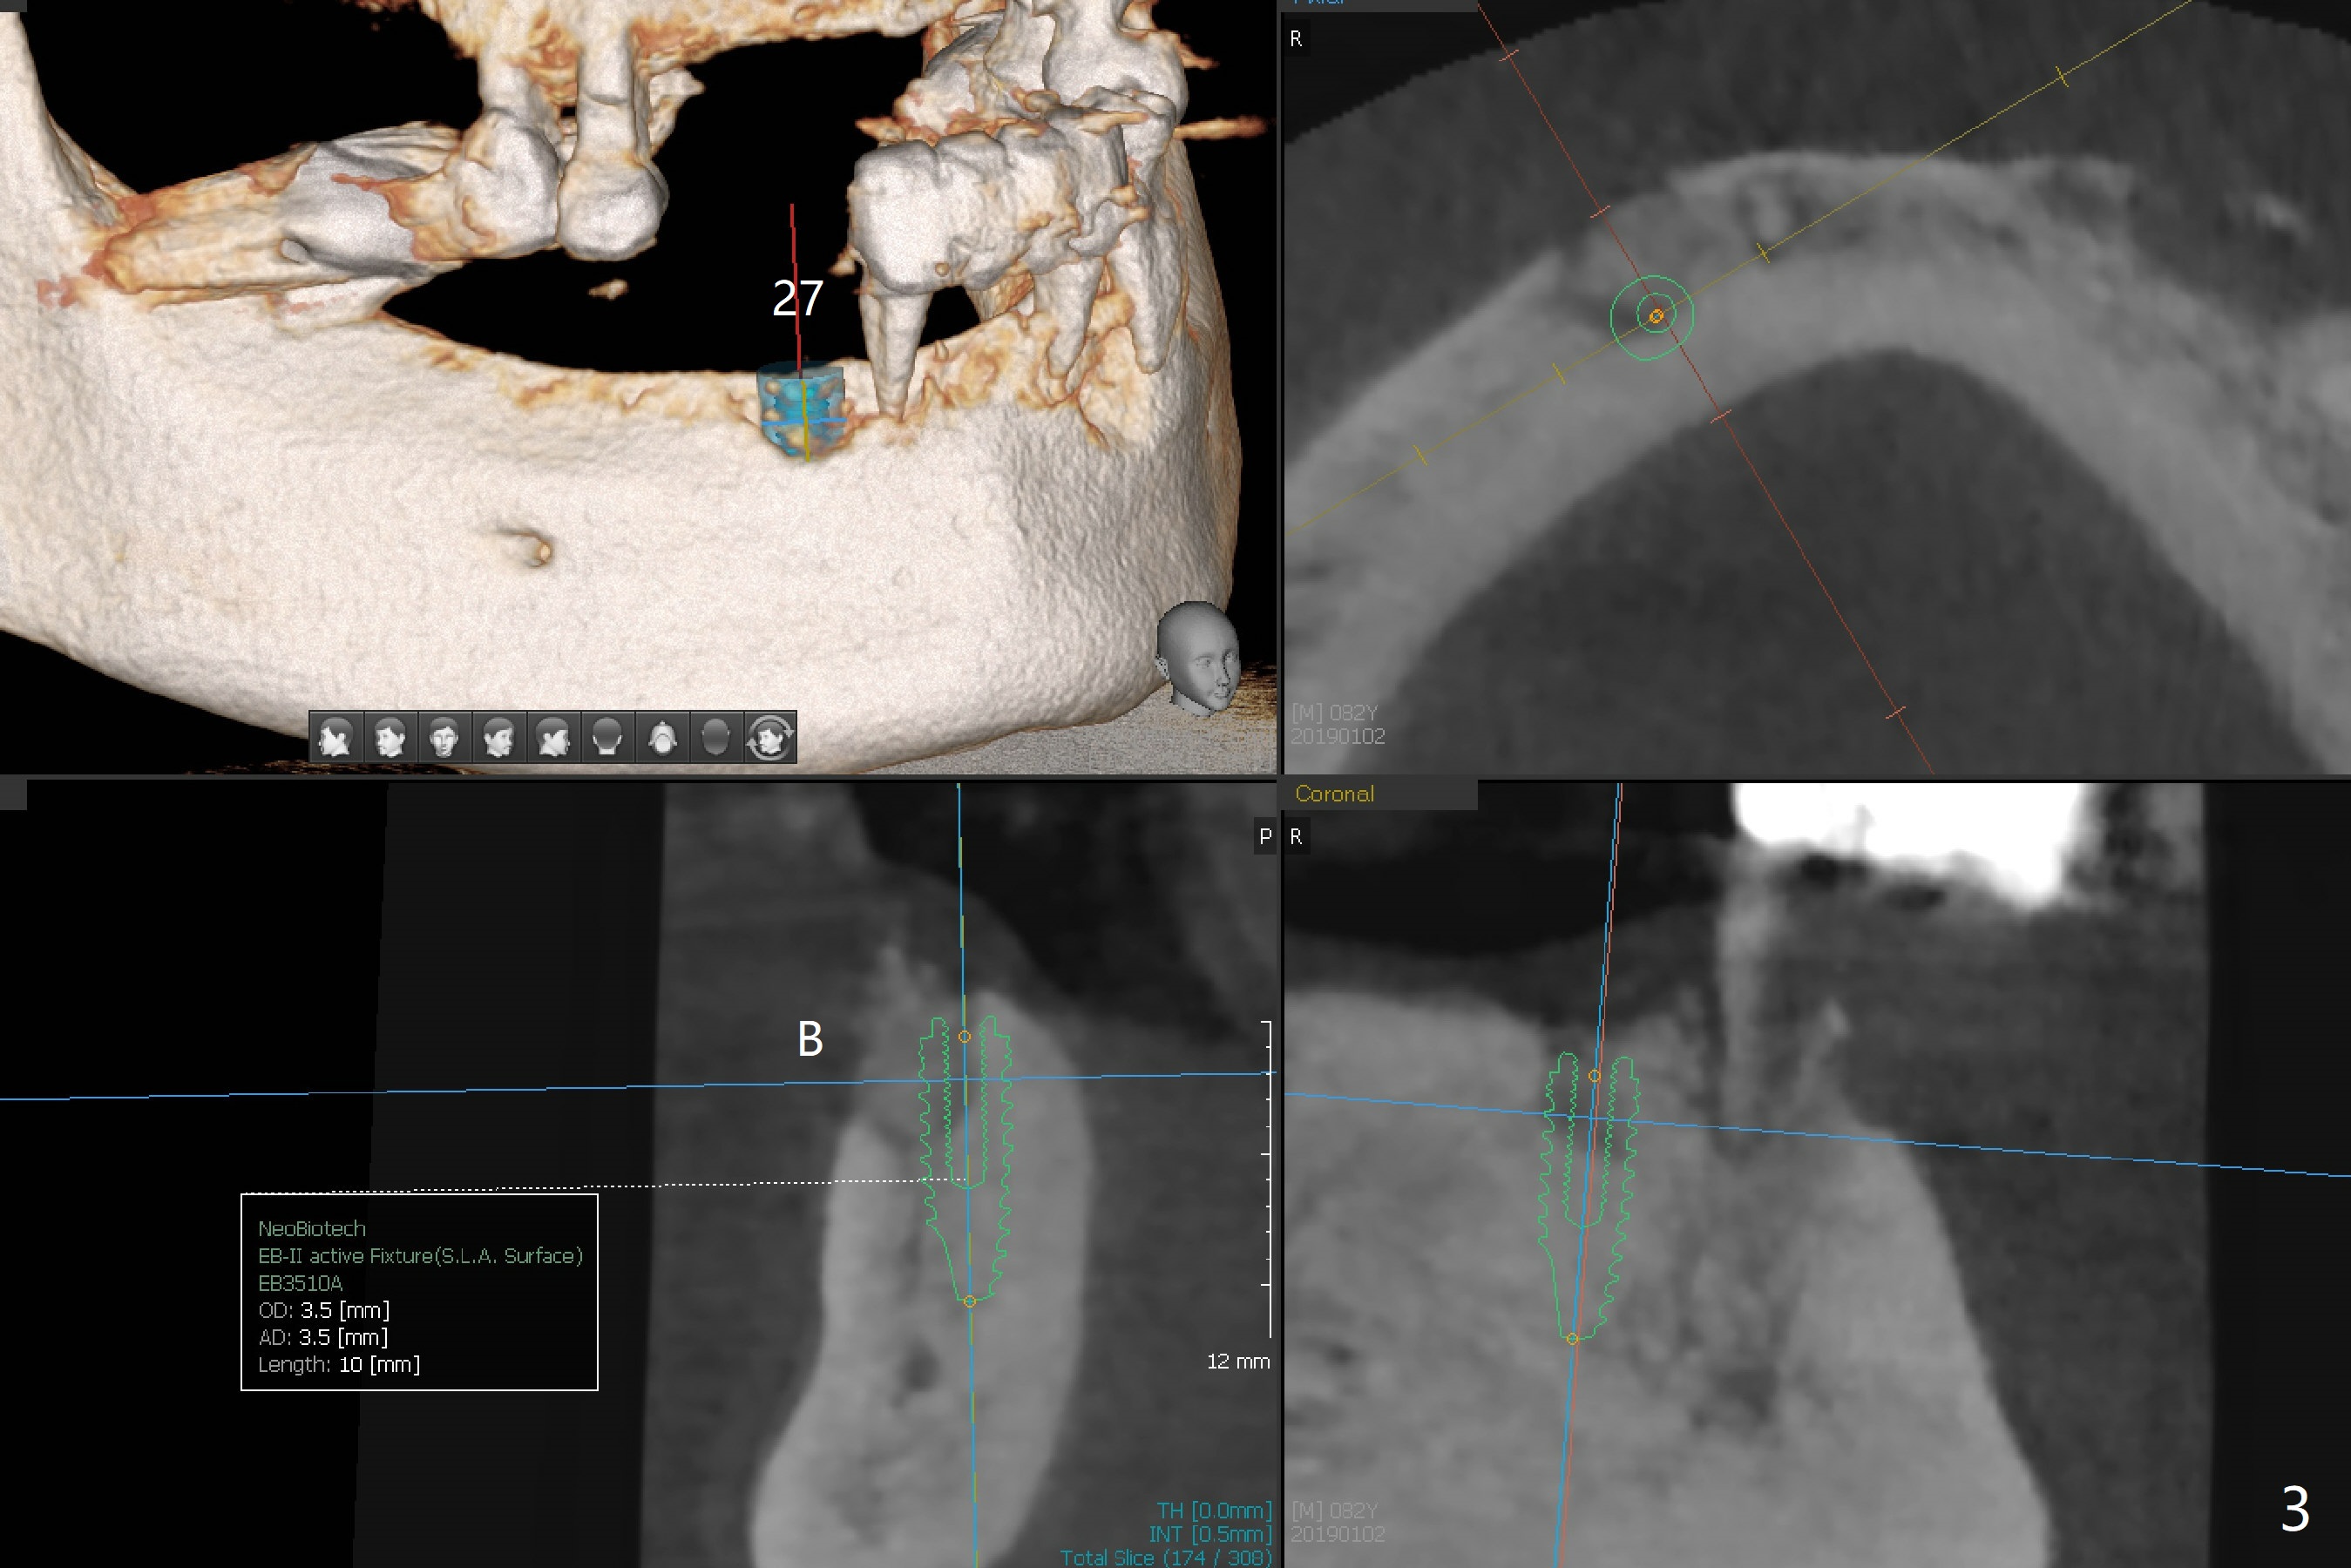

Abutments for Lower RPD

A 82-year-old man with poor dentition (upper and lower RPDs) returns to clinic for definitive treatment 2 weeks post socket preservation at #27 (with loss of the buccal plate, Fig.1). The bridge at #23-26 is mobile and to be removed. The tooth #22 appears to be restorable, but there is a buccal fistula (Fig.2 *). The root is out of the socket revealed by CBCT (Fig.5). Bone loss is severe at #20 (Fig.1,6). Three implants are going to be placed with guide at 27 or 26, 22 and 20 (Fig.3-6) with ball abutments for the lower RPD retention. Later the tooth #18 is found to be nonsalvageable.